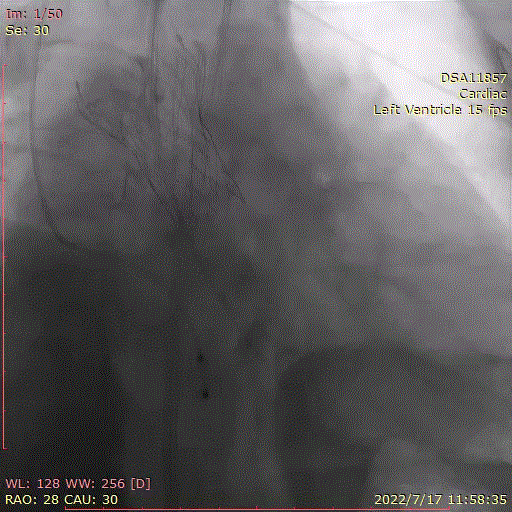

术中首先行冠脉造影术,造影提示右冠近中段严重狭窄,于病变处植入支架一枚。植入后造影显示,无残余狭窄及夹层,前向血流TIMI3级。

冠脉造影,支架植入

主动脉根部造影示主动脉瓣重度狭窄,采用20mm球囊预扩,有轻微腰征,无造影剂渗漏。

主动脉根部造影